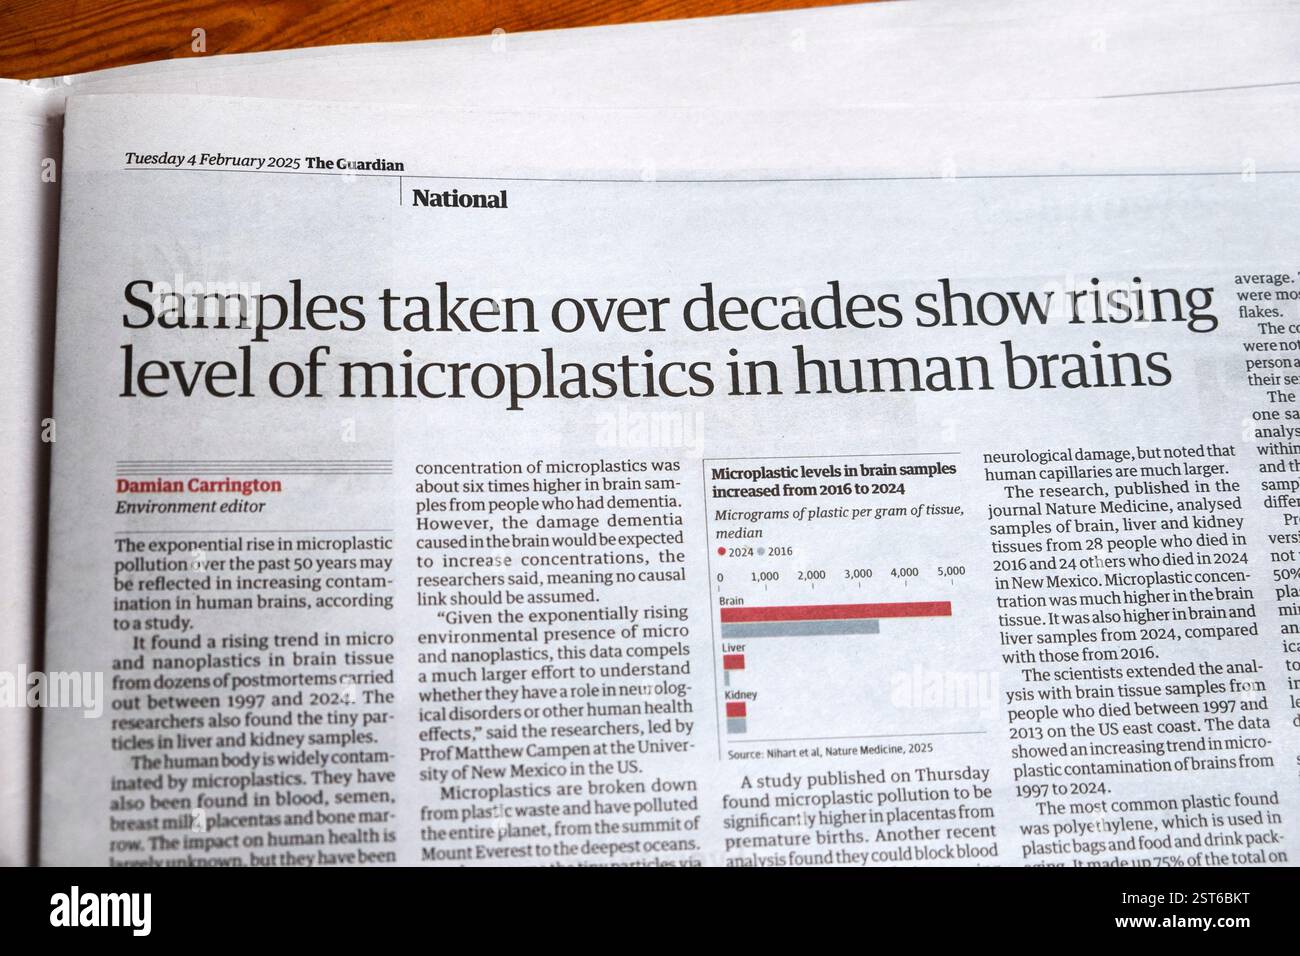

"I campioni prelevati nel corso di decenni mostrano un aumento del livello di microplastica nel cervello umano" Guardian testata impatto salute articolo 4 febbraio 2025 Regno Unito Foto Stockhttps://www.alamy.it/image-license-details/?v=1https://www.alamy.it/i-campioni-prelevati-nel-corso-di-decenni-mostrano-un-aumento-del-livello-di-microplastica-nel-cervello-umano-guardian-testata-impatto-salute-articolo-4-febbraio-2025-regno-unito-image651676252.html

"I campioni prelevati nel corso di decenni mostrano un aumento del livello di microplastica nel cervello umano" Guardian testata impatto salute articolo 4 febbraio 2025 Regno Unito Foto Stockhttps://www.alamy.it/image-license-details/?v=1https://www.alamy.it/i-campioni-prelevati-nel-corso-di-decenni-mostrano-un-aumento-del-livello-di-microplastica-nel-cervello-umano-guardian-testata-impatto-salute-articolo-4-febbraio-2025-regno-unito-image651676252.htmlRM2ST6BKT–"I campioni prelevati nel corso di decenni mostrano un aumento del livello di microplastica nel cervello umano" Guardian testata impatto salute articolo 4 febbraio 2025 Regno Unito